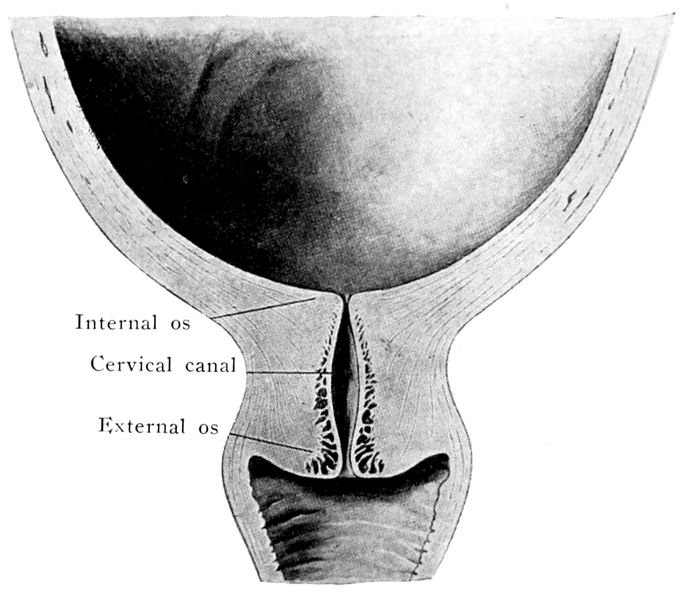

The bag of waters begins to act on the cervix |

111 |

| |

| 36. |

The effect of the pains. The cervix before labor begins |

112 |

| |

| 37. |

The effect of the pains. The cervix begins to be “effaced” |

112 |

| |

| 38. |

The effect of the pains. The cervix is effaced, and the dilatation of the os begins |

113 |

| |

| 39. |

The effect of the pains. The cervix is effaced and the os continues to dilate |

113 |

| |

| 40. |

The cervix is effaced and the os dilated |

115 |